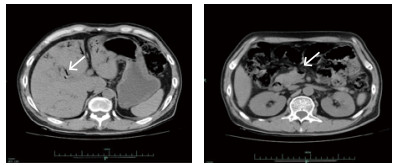

入院后在中心静脉压、有创动脉血压、每小时尿量、血气分析等严密监测下扩容补液、纠正酸中毒、亚胺培南西司他丁钠针联合利奈唑胺针抗感染、持续性血液净化纠正内环境等综合治疗后,病情逐渐好转,尿量增加,酸中毒纠正,肾功能恢复,血钠、血酮体降至正常,血糖控制在10 mmol/L以下。入院后第2天发现患者右上肢肢端温度低,右拇指发黑,血管超声示右上肢肱动脉远心端管腔闭塞,食道超声提示主动脉瓣近无冠瓣基底部可见4 mm×4 mm中等回声。入院第3天复查CT示肠系膜上静脉及门静脉积气消失(图 2)。入院第4天血培养回报:左侧外周为产气肠杆菌,右侧外周为草绿色链球菌,根据药敏结果调整抗菌药物为头孢曲松针联合左氧氟沙星针治疗,患者病情逐渐好转后出院。

| 图 2 入院第3天复查CT结果 |